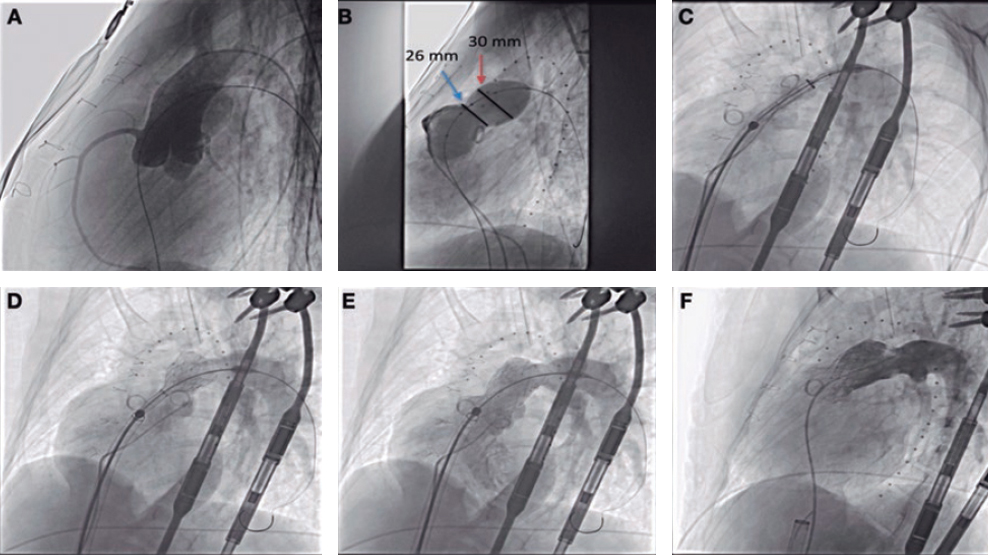

This is the case of a 51-year old male without a past medical history. One month before his admission he experienced fast heart palpitations associated with diaphoresis, nausea and vomit. Both the electrocardiogram and the Holter monitor showed recurring episodes of monomorphic ventricular tachycardia (figure 1). The physical examination confirmed the presence of an aortic ejection murmur exacerbated when performing the Valsalva maneuver. The transthoracic echocardiography showed obstructive asymmetric septal hypertrophy with a 32-mm maximum septal diameter (figure 2A), a 65-mmHg gradient in the left ventricular outflow tract, and systolic anterior motion of the mitral valve with moderate regurgitation. The cardiovascular magnetic resonance imaging confirmed the presence of extensive myocardial fibrosis as a risk factor of sudden death (figure 2B and video 1 of the supplementary data). Amiodarone and propranolol were prescribed, and an automatic defibrillator was implanted as a secondary prevention measure. The patient was readmitted to the hospital 4 months later with signs of electrical storm with multiple discharges provided by the device implanted. Deep sedation, mechanical ventilation, and hemodynamic support were administered, and the stellate ganglion was blocked. However, the patient progression was poor with persistent episodes of ventricular tachycardia that triggered the mapping of cardiac electrophysiology using the CARTO 3 system (Biosense Webster, Israel). The ablation of a septal macroreentrant circuit of the left ventricle associated with the clinical ventricular tachycardia was unsuccessful (figure 2C).

A bail-out alcohol septal ablation procedure was attempted that showed a 65-mmHg intraventricular gradient. After the 110-mmHg extrasystole bubble contrast was injected to choose the target septal branch (figure 3) followed by the injection of 0.1 mL of alcohol per millimeter of contrasted septum. In the echocardiography a 23 mm contrasted septum was measured, and 2.3 mL of alcohol were administered in the second septal branch.

Figure 3. A: coronary angiography. B: injection of bubble contrast in the second septal branch. C: contrast enhancement of the susceptible septal region (arrow). D: over-the-wire balloon used for the administration of alcohol.